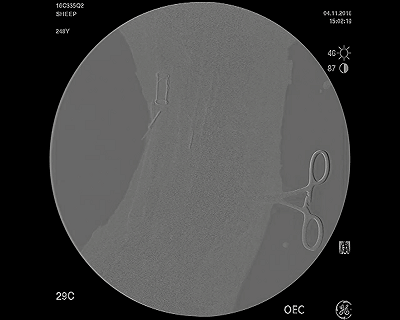

下行靜脈造影圖,顯示VenoValve關(guān)閉,防止靜脈血液反流